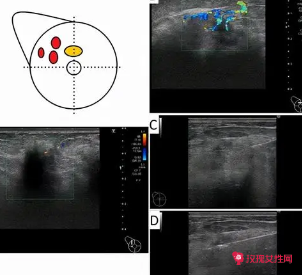

一般做假体隆胸后是不会影响乳腺彩超检查的。假体隆胸通常采用硅胶或者水凝胶,可以让原本平坦的胸部显得更有型,从而提高患者的整体美感;硅胶或者水凝胶具有很好的可塑性,手感也很自然,并且对乳腺彩超没有影响。

假体隆胸后做乳腺彩超检查一般不受影响。假体是安全的,对乳腺导管以及乳腺健康没有影响,同时乳腺彩超检查也不会使假体产生移位或者脱落的情况。如果做完假体隆胸半年之内出现乳房疼痛,这种情况是正常的,

这是因为胸部对假体有排斥感,相应的会出现轻微的'胀痛,切忌用手触碰。

做假体隆胸后通常对彩超乳腺检查是没有影响的。假体里边的硅胶成分含有硅酸凝胶,膨体聚四氟乙烯,在做彩超检测之间会穿透假体的材质,并不会影响彩超检查所造成的影像反应,做完假体隆胸后要多注意伤口的愈合,

短时间内不要用手加压。平时要保护好胸部,避免创伤导致胸部感染。

做假体隆胸后对彩超乳腺检查一般没有影响。通过做乳腺彩超检查,可以观察到胸部内有假体,也可以了解到胸部的情况,不会对检查造成影响,做了假体隆胸手术之后,也需要定期去医院做乳腺检查,观察是否存在疾病。假体包括硅胶和膨体,需要经过全面消毒之后放入到胸大肌部位,具有塑形的功效,周围也具有脂肪包裹。

做了假体隆胸大多是可以通过彩超查乳腺增生的。做彩超的时候假体并不会影响检查结果,也不会遮盖住乳腺的部位。如果乳房出现了胀痛的情况,就可以到医院做彩超进行检查。假体隆胸是目前来说丰胸比较流行的一种方法,是将假体硅胶植入到胸里,使胸变得丰盈饱满,效果是永久性的,只要假体不出现变形和变质的情况,是可以不取出体外的。

一般假体都是硅胶膜内充水凝胶做的,因此不会影响诊断结果。彩超是目前最简便的一种检查方式,他对你没有什么影响,也不受什么限制,丰胸之后是可以做乳腺彩超的,假体或者说是自体填充的物质,通过彩超是可以看得出来的。假体丰胸是将丰胸假体置放在乳腺下或者是胸大肌下的,而把假体植入这两个部位的'选择,

是因为它们位于乳腺的后面,这样可以使乳腺不受假体的影响。建议术后大概2周之后可以考虑做静态按摩,不要做动态按摩,静态按摩就是趴在平的、硬的床板上进行静态压迫,有助于胸部柔软度的恢复。